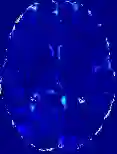

Accurate infarct segmentation in non-contrast CT (NCCT) images is a crucial step toward computer-aided acute ischemic stroke (AIS) assessment. In clinical practice, bilateral symmetric comparison of brain hemispheres is usually used to locate pathological abnormalities. Recent research has explored asymmetries to assist with AIS segmentation. However, most previous symmetry-based work mixed different types of asymmetries when evaluating their contribution to AIS. In this paper, we propose a novel Asymmetry Disentanglement Network (ADN) to automatically separate pathological asymmetries and intrinsic anatomical asymmetries in NCCTs for more effective and interpretable AIS segmentation. ADN first performs asymmetry disentanglement based on input NCCTs, which produces different types of 3D asymmetry maps. Then a synthetic, intrinsic-asymmetry-compensated and pathology-asymmetry-salient NCCT volume is generated and later used as input to a segmentation network. The training of ADN incorporates domain knowledge and adopts a tissue-type aware regularization loss function to encourage clinically-meaningful pathological asymmetry extraction. Coupled with an unsupervised 3D transformation network, ADN achieves state-of-the-art AIS segmentation performance on a public NCCT dataset. In addition to the superior performance, we believe the learned clinically-interpretable asymmetry maps can also provide insights towards a better understanding of AIS assessment. Our code is available at https://github.com/nihaomiao/MICCAI22_ADN.